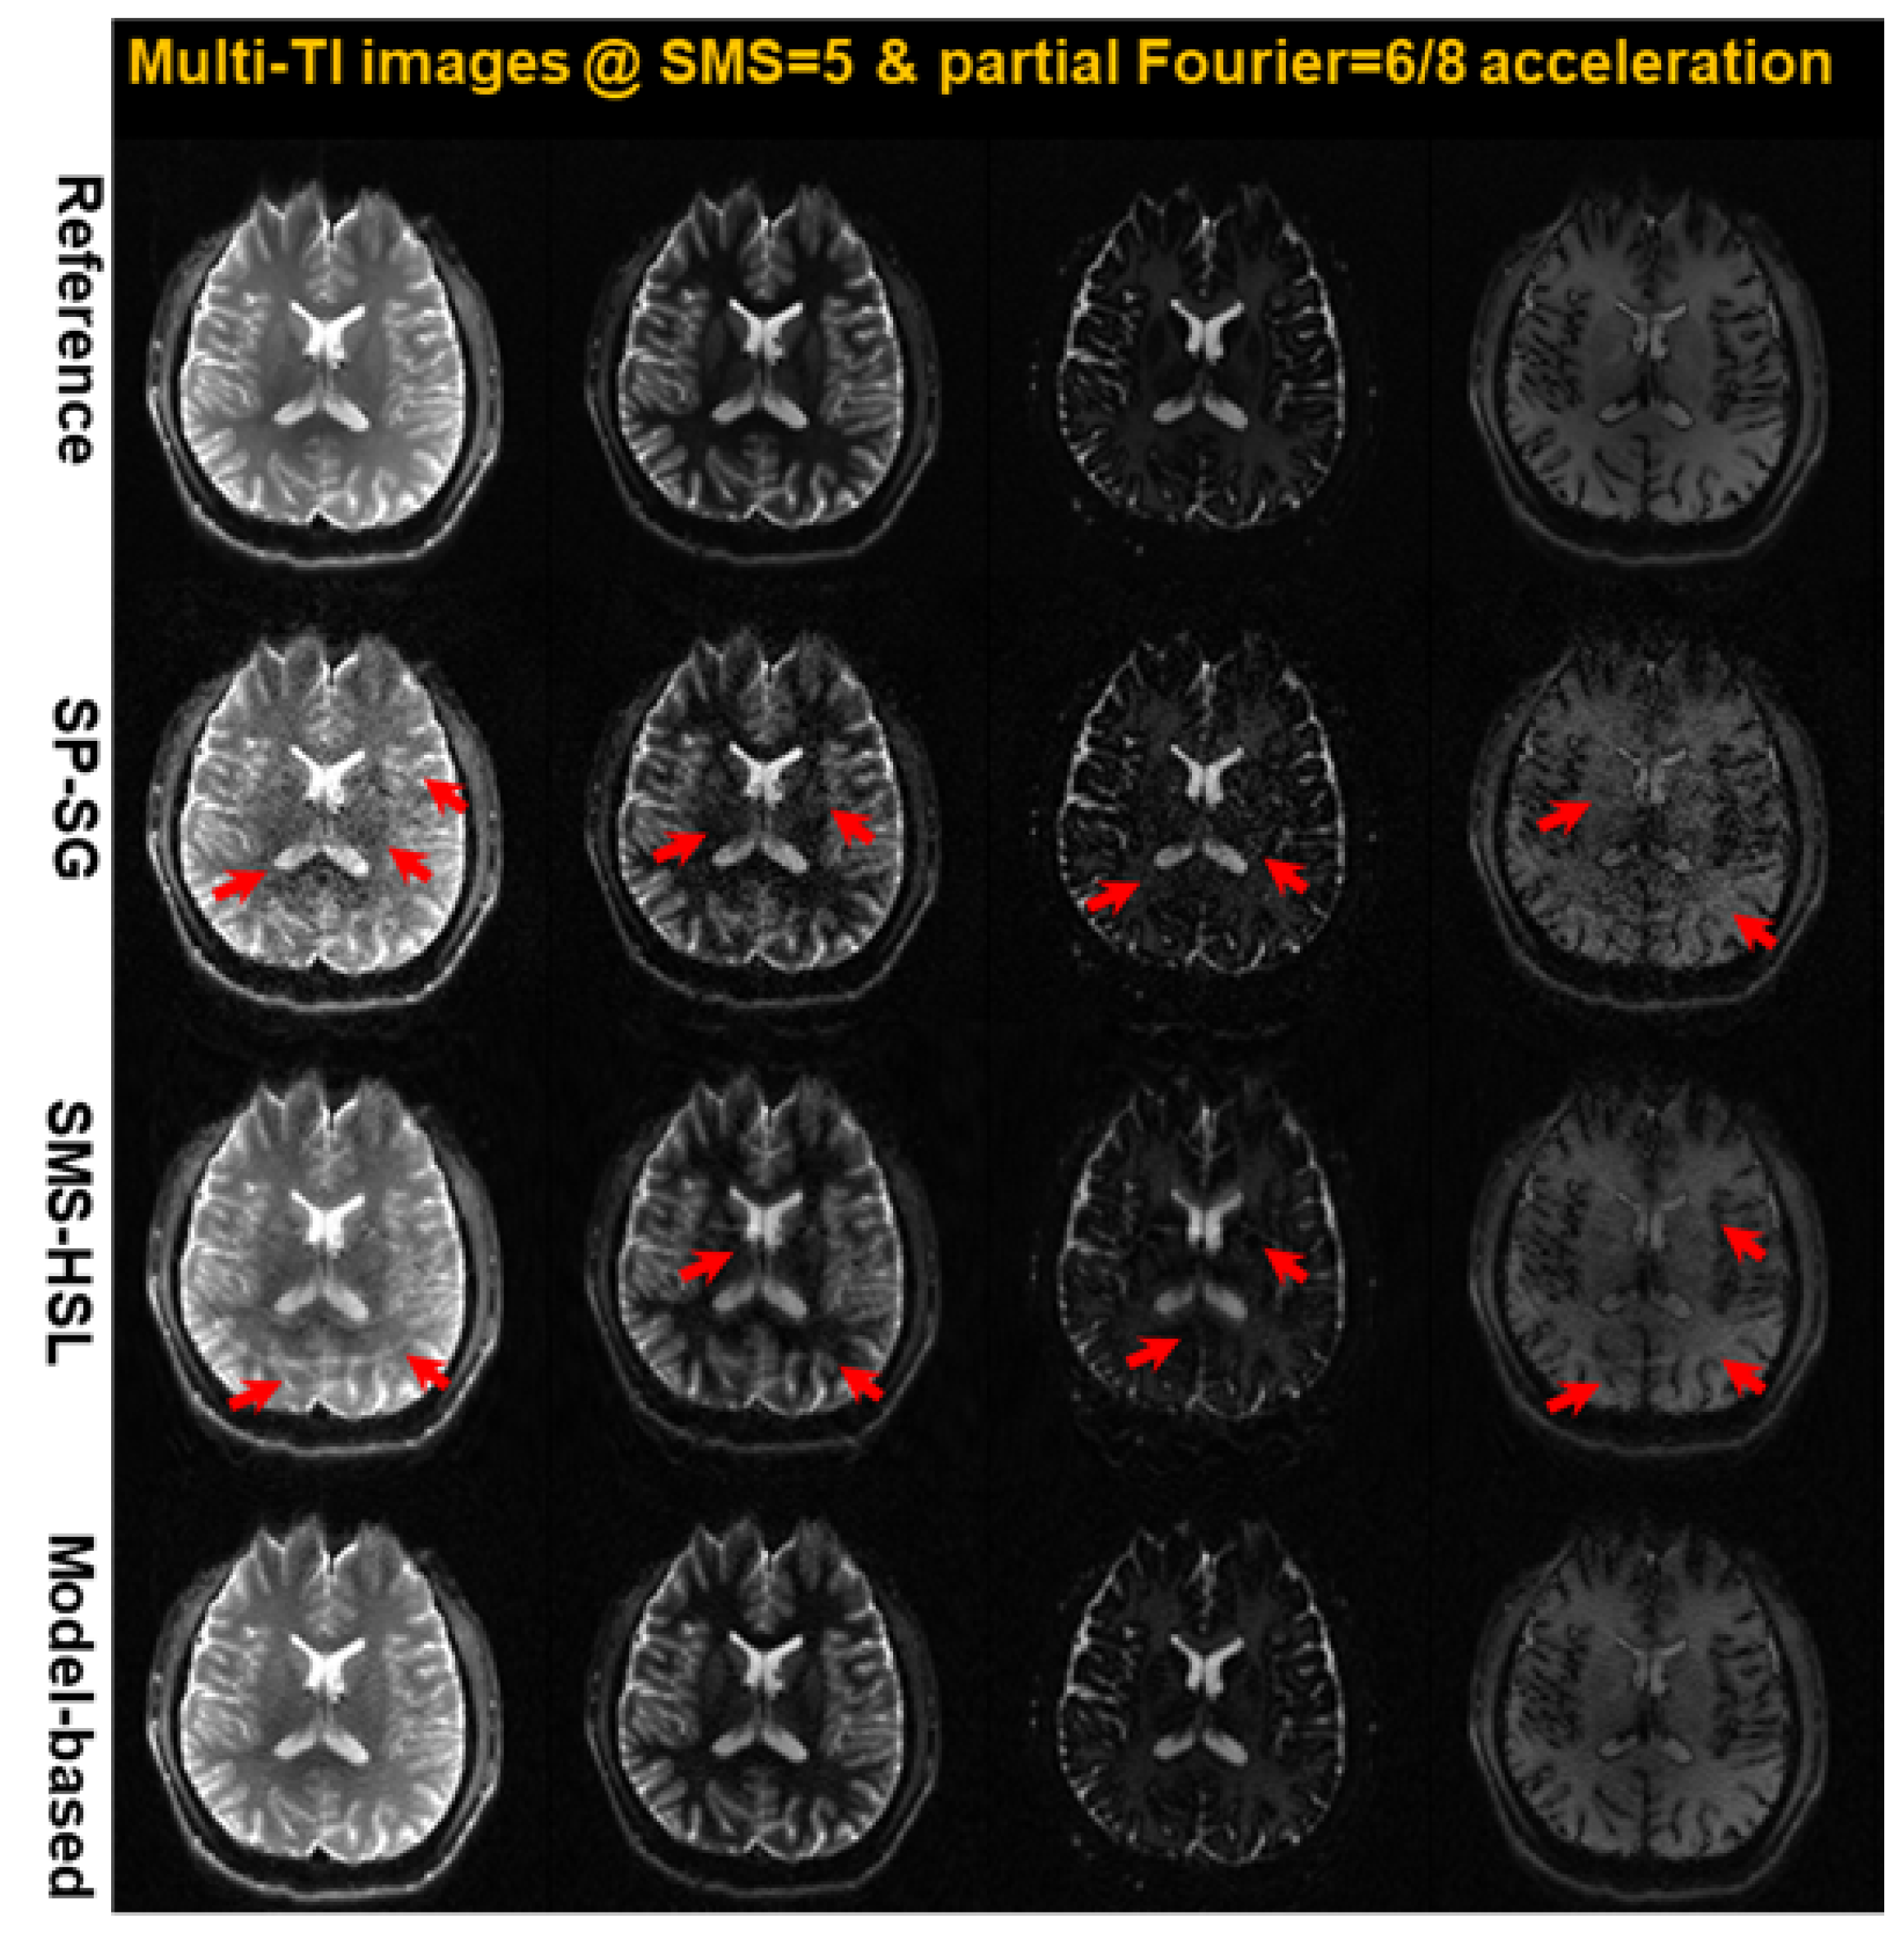

- IR-SE-EPI: Fully sampled brain k-space data were collected by a 3T Prisma equipped with a 20-channel receiver head coil using a 2D IR-SE-EPI sequence. The following parameters were used for IR-SE-EPI: FOV = , matrix size = , slice thickness = 3 mm, number of slices = 30, TR/TE = 20,000 ms/27 ms, 16 IR scans (TI = 34, 100, 200, 300, 400, 500, 600, 700, 800, 900, 1000, 1200, 1400, 1600, 1800, and 2000 ms), and partial Fourier (PF) = 62.5%. To compare the slice unaliasing performance of the current state-of-the-art techniques listed in the Introduction, our experiments used five slices (1st, 7th, 13th, 19th, and 25th slices) from this dataset with ab SMS factor of 5.

4.2. Retrospective Studies: SMS Simulation

4.3. Prospective Studies: Experimental Validation